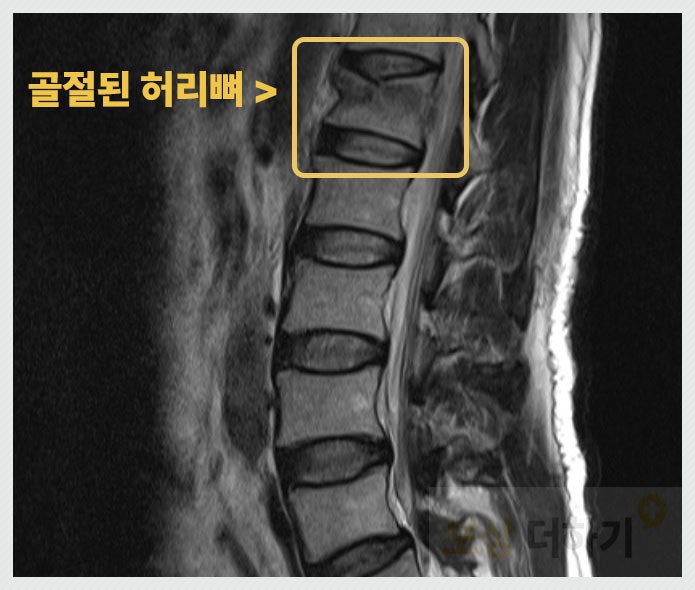

허리 뼈는 엉덩방아 찧을 때와 같이 외부의 충격을 받게 되면 찌그러지듯 골절이 됩니다. 아래 사진을 보시면 마치 음료수 캔이 찌그러지는 것과 같은 모습이죠.

● 요추 1번 압박골절 허리 뼈 1번 골절 진단이 나왔고 주치의, 가족과 상의하여 척추체 성형술을 시행 받기로 하셨어요.

장해 평가 : 압박률 27%, 후만각 27도로 지급률은 30%에 해당